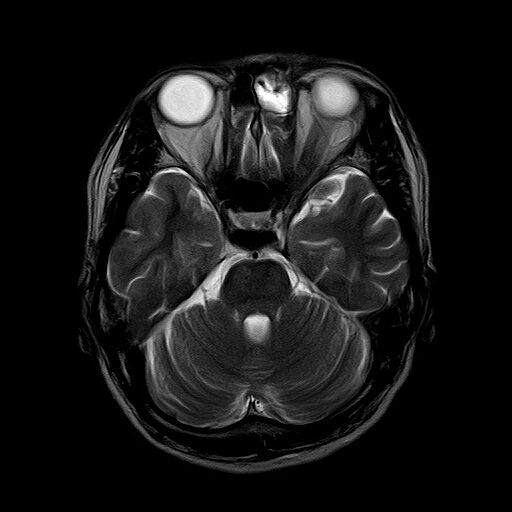

症例は30代の男性。数か月前から続く左目の違和感と頭痛で眼科を受診。眼科精査で異常なく、頭の精査目的に当院紹介となった方です。頭痛は左眉の上に限局しており、下を向くと痛みが増強されました。ここ数か月以内に、風邪に罹患した既往なし。頭部MRI・MRAを撮影し、脳や頭の血管には異常所見は認めませんでしたが、副鼻腔内が白く光って見えており、副鼻腔炎と診断しました。

とくに両側の上顎洞(頬の部分)と左前頭洞(眉の部分)が白く光っており、浸出液や膿がたまっている状態です。